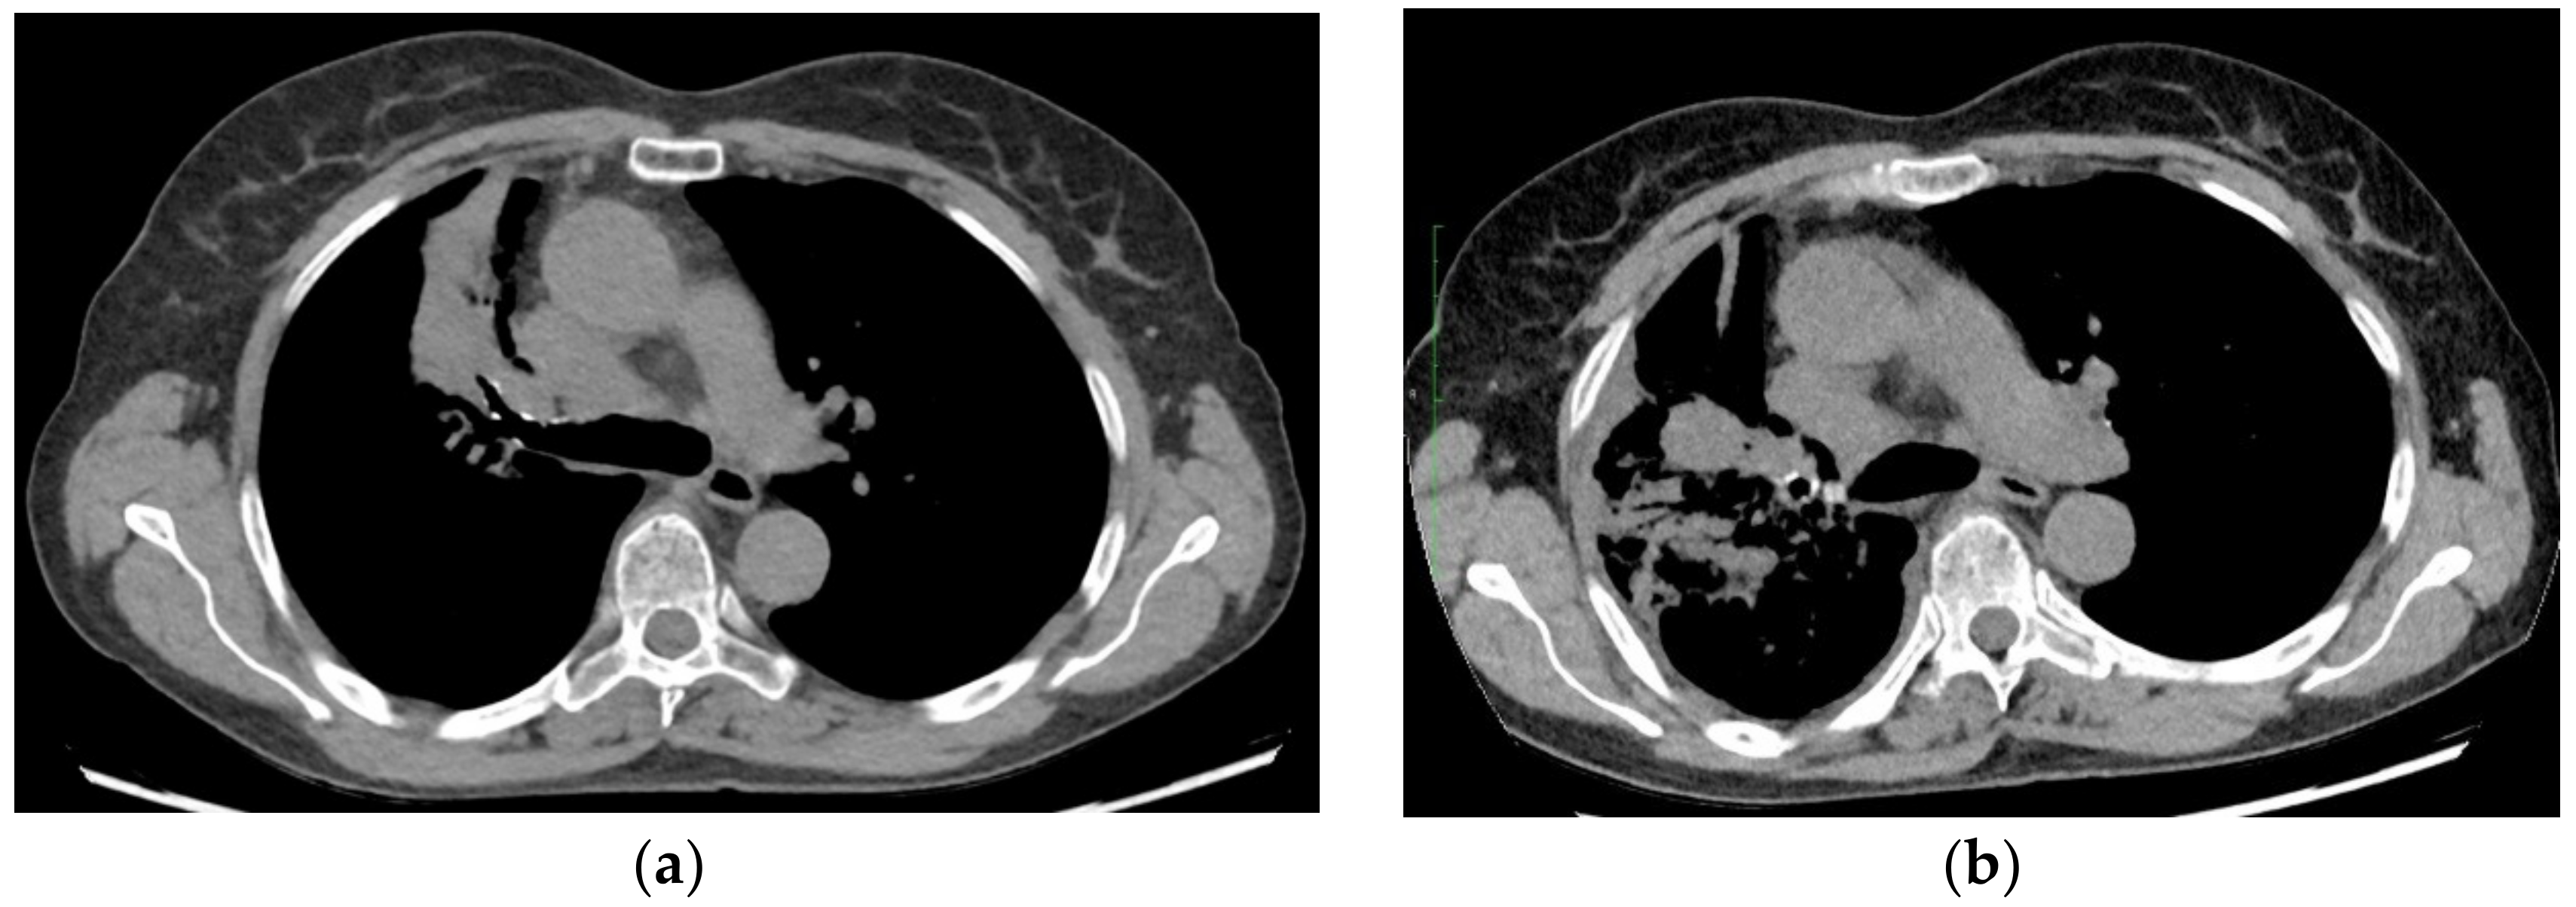

2. Case Presentation